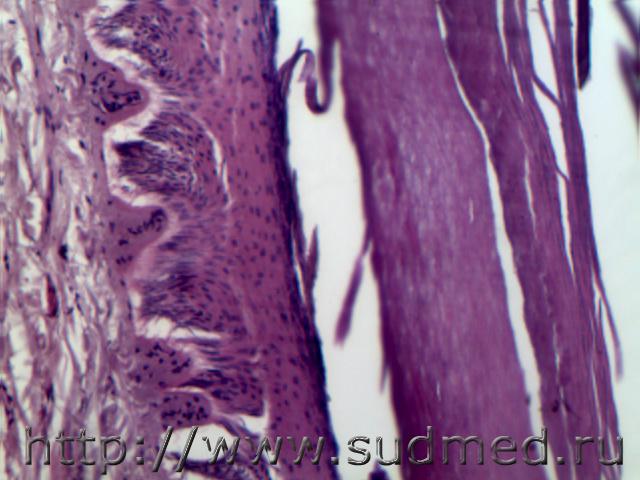

Мягкая странгуляционная борозда при повешении - роговой слой отсутствует, ядра клеток эпидермиса вытянутой формы расположены косо и параллельно поверхности кожи, сосочковый слой сглажен, потовые железы уплощены, волосяной фолликул и сальные железы умерено уплощены, на периферии венозное полнокровие.Прижизненные признаки - кровоизлияние в подкожной клетчатке, нервный стволик разрыхлен.